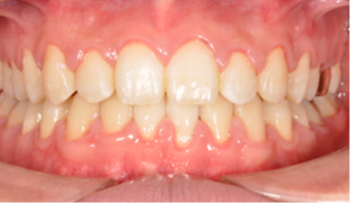

​​​​​​​Case 01. 덧니 & 치열 불규칙

덧니가 있거나 치열이 불규칙한 경우, 심미적으로도 보기에 좋지 않지만, 기능적으로도 본연의 역할을 상실하게 됩니다.

이 경우 교정 치료 방법은 크게 치아를 빼고 하는 방법과 치아를 빼지 않고 교정하는 방법으로 나뉩니다.

교정 치료 Before & After

• 덧니 & 치열 불규칙 교정 치료 전

Before

• 덧니 & 치열 불규칙 교정 치료 후

After